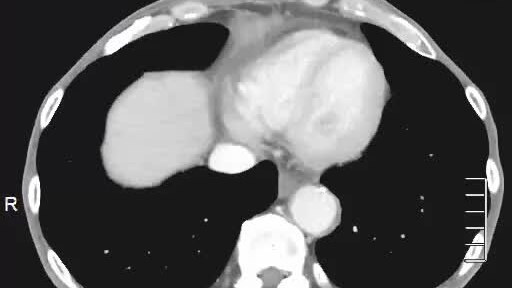

Если вы прошли КТ